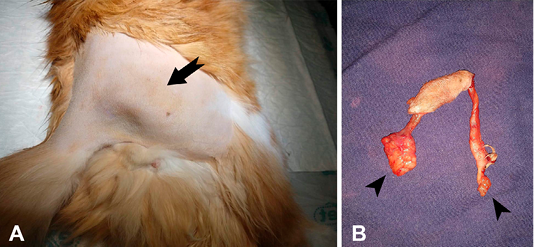

Figure 1

Trichogranuloma in a cat. A. Right pelvic limb showing a firm elastic nodular mass (arrow). B. Surgical excision of the nodular mass showing two tubelike structures (fistulous tract) with blind edges (arrow heads).